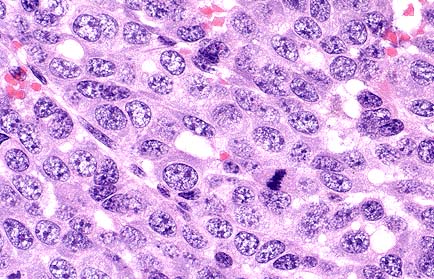

Higher magnification of the field shown above. Neoplastic cells are polygonal with moderate amounts of eosinophilic cytoplasm, and prominent oval to round nuclei. (HE, 400X, 54K)

Essential microscopic features are those of a circumscribed, non-encapsulated, multi-lobulated, nodular mass effacing the gland. Lobules are composed of a uniform population of cells forming densely cellular sheets and thick cords which surround multiple, variably-sized spaces that are either empty or contain variable amounts of blood and/or fibrin, proteinaceous secretory material and degenerate cells. In some areas, the cells form poorly-defined tubular structures. Cells are polygonal with indistinct margins, abundant eosinophilic cytoplasm and oval to round nuclei with clumped chromatin and occasionally 1-2 prominent nucleoli. Mitotic figures number 6 to 12 per HPF. Focal areas of necrosis occur within lobules.

Utilizing the SSNDC criteria, mammary adenocarcinoma is defined as arising from mammary gland epithelium. There is loss of lobular architecture, invasion of surrounding tissue, cellular pleomorphism, and frequent mitoses. These tumors may have a variety of histologic patterns, many of which may occur within the same tumor, including tubular, papillary, cystic, solid, comedo, and undifferentiated. The glandular components of these tumors may be associated with a myoepithelial component.